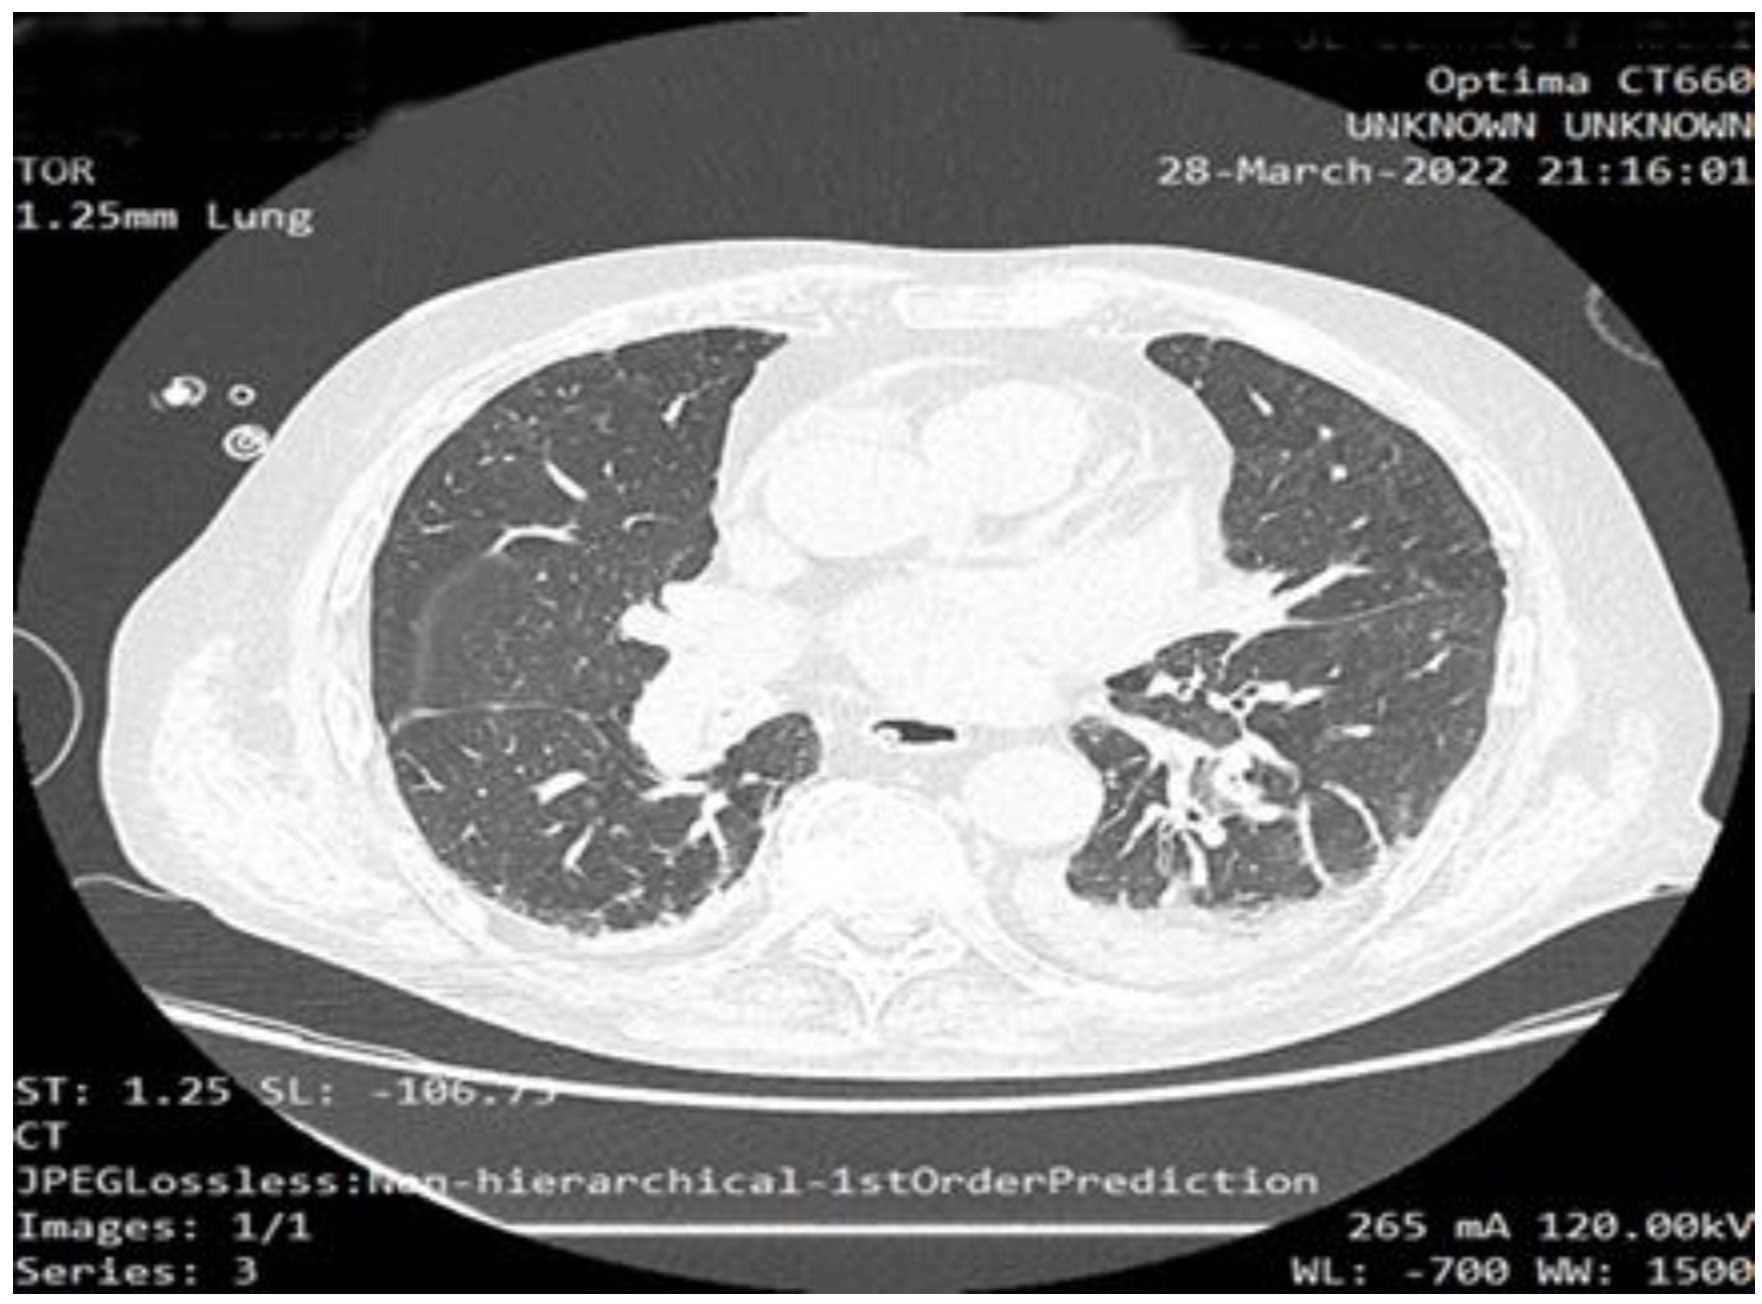

2. Case Report